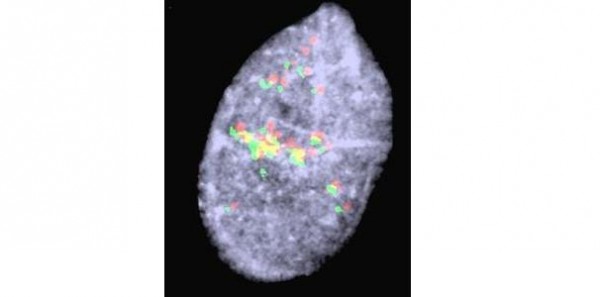

FISH showing PAX-FOXO1 amplification in alveolar rhabdomyosarcoma